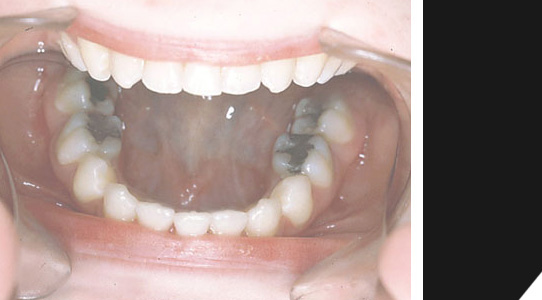

Eine deutliche Fehlstellung des Frontbereichs...

Im unteren Bereich sind nur drei Frontzähne vorhanden...

Zudem kommt noch ein starker Überbiss...